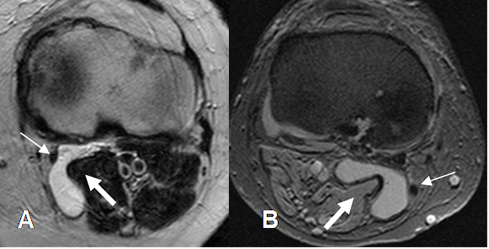

En la RM se aprecia como lesión quística posterior. Puede presentar signos de sinovitis o cuerpos libres en su interior. (Fig 176 a 179).

Fig 176. Quiste de Baker.

A: RM axial en T2 y B: RM axial en FFE. Lesión quística entre los músculos gemelo interno (Flecha gruesa) y semimembranoso (Flecha delgada), que corresponde a quiste de Baker.